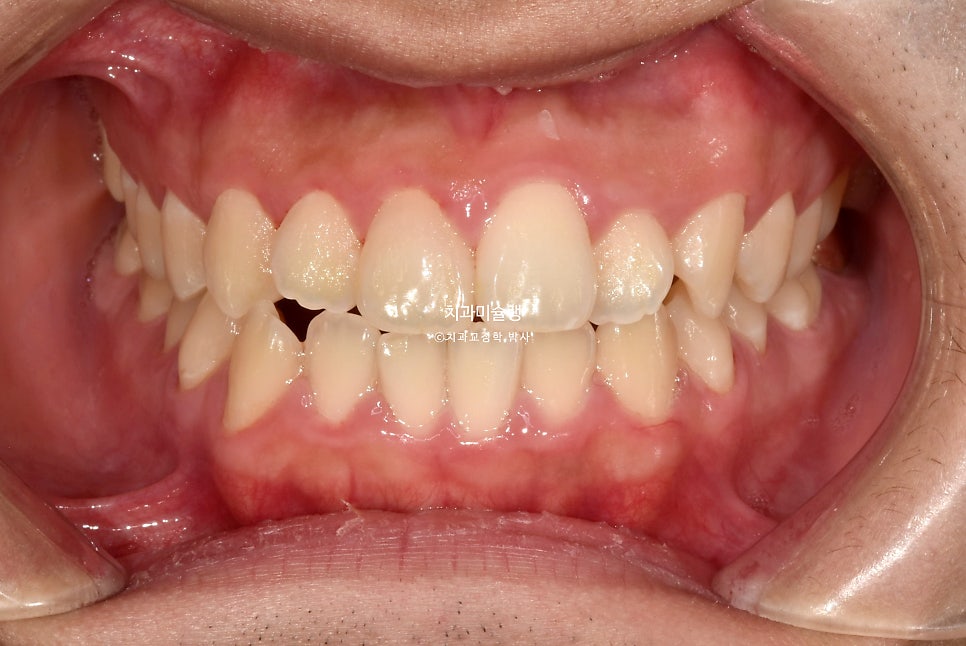

초진 시 구강 상태

2024년 봄 초진

2024년 봄 교정치료를 위해 내원한 환자분 입니다.

중심선 불일치, 반대교합, 덧니 등이 보입니다.

앞니가 뻗친 돌출 입니다.

그에비하면 어금니는 배열도 좋고 교합도 좋은 편이죠.

입이 잘 안다물어질 정도의 돌출입이며 웃을때 잇몸이 과하게 보이는 거미스마일도 있습니다.